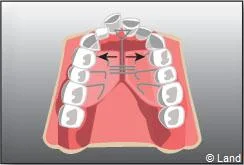

De plus, il est opportun de corriger très tôt certaines malpositions. Les appareils généralement utilisés sont amovibles avec une armature en résine, mais peuvent aussi être fixes à l’aide de bagues sur les premières molaires définitives.. Suivant leurs conceptions et la manière dont ils sont portés, ils auront une action sur la position des dents mais aussi sur la croissance.